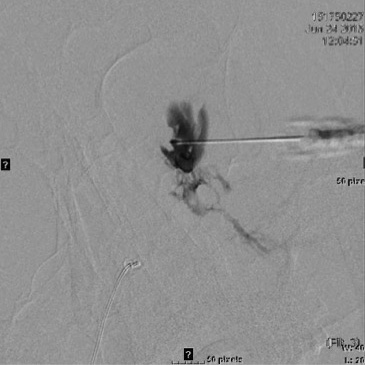

If treating a VM, as in treating a VM anywhere else in the body, a venogram under fluoroscopy is useful to assess the size of the lesion, the routes of venous drainage, and the rate of run off. Using standard fluoroscopic guided sclerosant injection techniques, the foams are all very well visualized especially under subtraction technique.

MRI of large LM cyst (top), catheter passing through lower lid (left), cystogram (right).